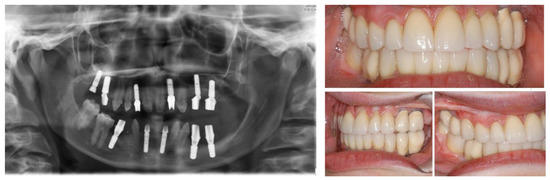

Figure 10.

Post-operative panoramic radiography.

Figure 11.

Definitive rehabilitation with dental-implant supported prosthesis.